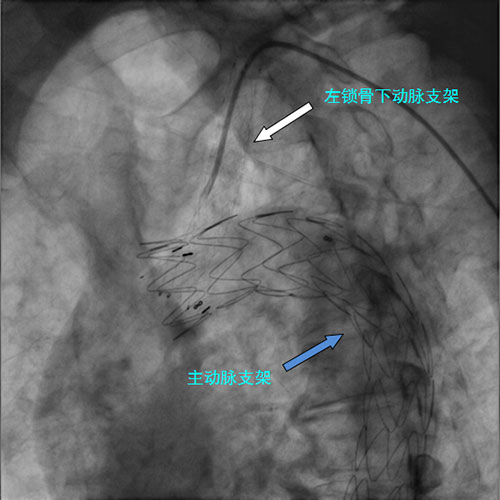

“烟囱”技术是在用覆膜支架覆盖主动脉夹层破口和左锁骨下动脉的同时,从左锁骨下动脉内送入另一枚支架和覆膜支架平行开口于主动脉,通过支架建立起主动脉到左锁骨下动脉的通道,这样可以巧妙地在封堵主动脉破口的同时,保存左锁骨下动脉的供血,避免脑梗死等严重并发症。在确定手术方案后,经过充分的术前准备,何鹏程主任带领喀地一院心内科介入团队在局部麻醉下应用经皮穿刺技术成功为该患者实施了”烟囱“主动脉腔内修复术,在主动脉及左锁骨下动脉各植入一枚支架,术后造影结果显示覆膜支架完全堵闭了主动脉破口,原来从主动脉真腔流向假腔的血流被完全阻断,而左锁骨下动脉血流通畅,患者双上肢血压完全一致,这意味覆膜支架在成功封堵主动脉破口的同时,又未对左锁骨下动脉血流造成任何损害,左上肢和左小脑的血流供应得到了保证,手术取得非常圆满的效果。

何鹏程主任介绍,主要应用于Debakey Ⅲ型主动脉夹层(也就是常规的降主动脉夹层)的主动脉腔内修复术属于心血管介入中的复杂手术之一,而涉及主动脉弓上分支(如颈动脉、锁骨下动脉)的主动脉腔内修复术更是由于其解剖复杂而难上加难,手术不仅要最大限度延长覆膜支架的覆盖范围以保证完全堵闭破口,又要最大限度避免覆膜支架对分支血流的影响,对手术技巧要求极高。